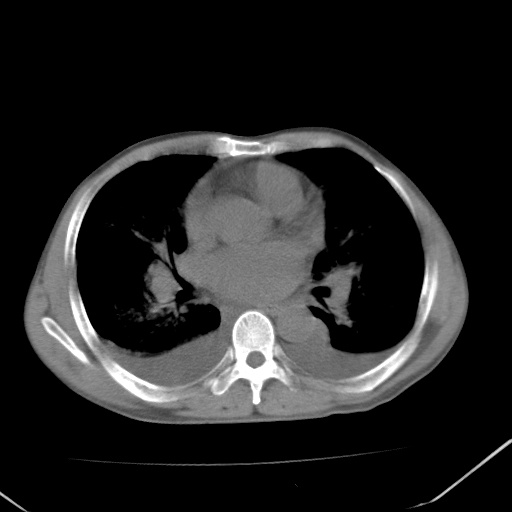

男、42岁、咯血3天。既往有甲亢、贫血、血尿蛋白尿史多年。血象:wbc:6.   中性粒:70.6%。

结合病史考虑双肺泡积血,双侧胸腔少量积液;肺水肿待排(肺水肿症状重)。

双肺堆成磨玻璃影,双测胸腔积液。考虑:肺水肿、间质性肺炎、真菌感染、ards、hiv感染、肺出血。

双肺野对称性磨玻璃影,分布于内中带,双侧胸水,患者有咯血。

双肺野广泛对称性磨玻璃影、实变影,以肺门为中心,主要分布于内中带,符合典型肺泡性肺水肿;伴双侧胸腔少量游离积液。结合患者既往病史且咯血就诊,支持多因素(尿毒症等)所致之肺水肿、肺出血、胸水;影像表现暂不考虑心源性水肿,且症状也不太符。需密切随诊结合临床治疗等进一步明确。

心影增大密度略低,双肺磨玻璃样高密度影及双侧胸腔积液,考虑心功能不全继发双肺肺水肿及双侧胸腔积液。心影密度略低,考虑贫血所致。